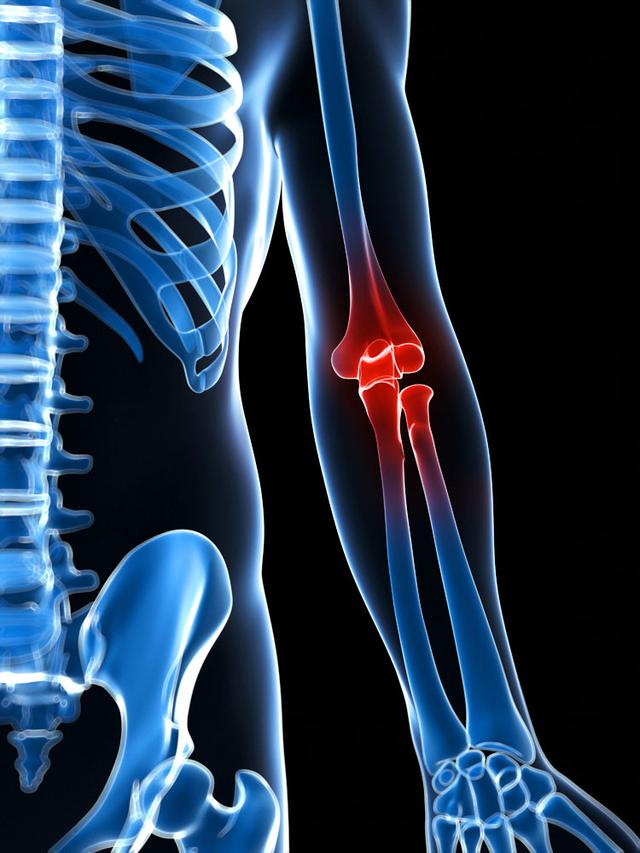

从一方面来说,人类是弱小的,容易生病,容易受伤,但从另一方面来说,人类也是强大的...